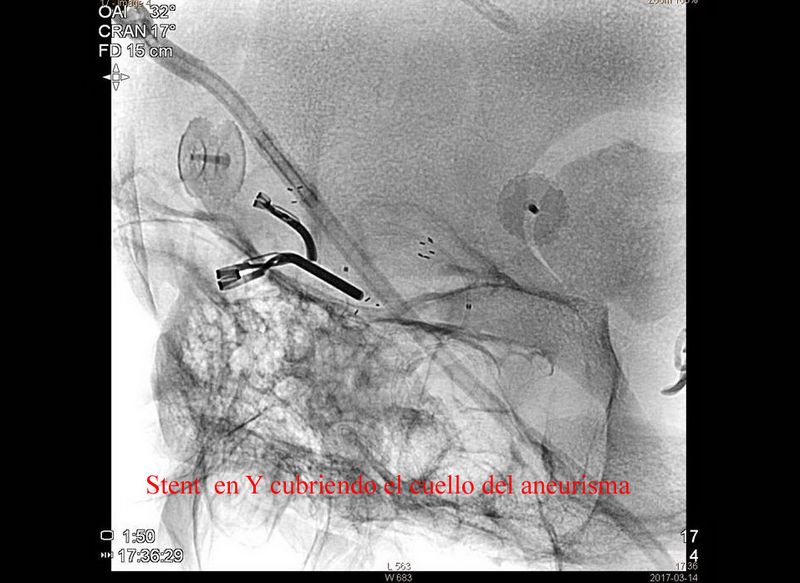

Aneurisma trat quirurgicamente